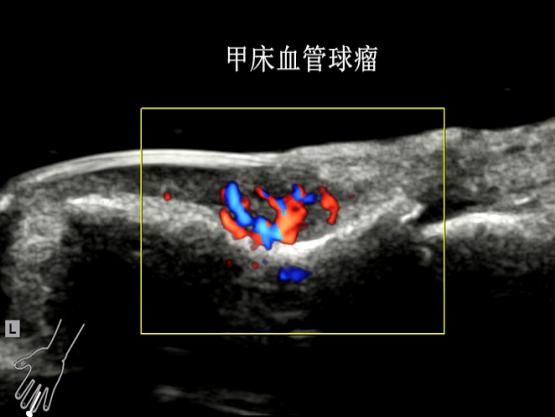

传统皮肤科诊断主要靠眼睛观察、手触摸,或取一点皮肤组织做病理检查,很难直接看到深层的情况。超高频超声(通常指频率在20MHz以上的超声),提供了新的观察维度——20MHz超高频超声可分辨0.1mm的病灶,70MHz超声高频超声可以分辨0.03mm病灶。

通过分析病灶的形态、边界特征和内部血供情况,医生能够更准确地区分炎症性病变、良性增生性病变与恶性肿瘤。

比如皮肤长了肿瘤,用超高频超声一看,就能知道病灶长在皮下哪一层、与周围血管、神经的毗邻关系,手术时怎样才能避开血管和神经。还有人得了“湿疹”“皮炎”,虽然临床诊断相对容易,但超高频超声能显示出真皮层有没有水肿、炎症范围有多大,帮助医生判断病情轻重,还能跟踪治疗后炎症是不是在消退。甚至像一些肉眼无法观察的部位,比如 “灰指甲”,超声也能穿透指甲,看看甲板下有没有真菌破坏的空洞。